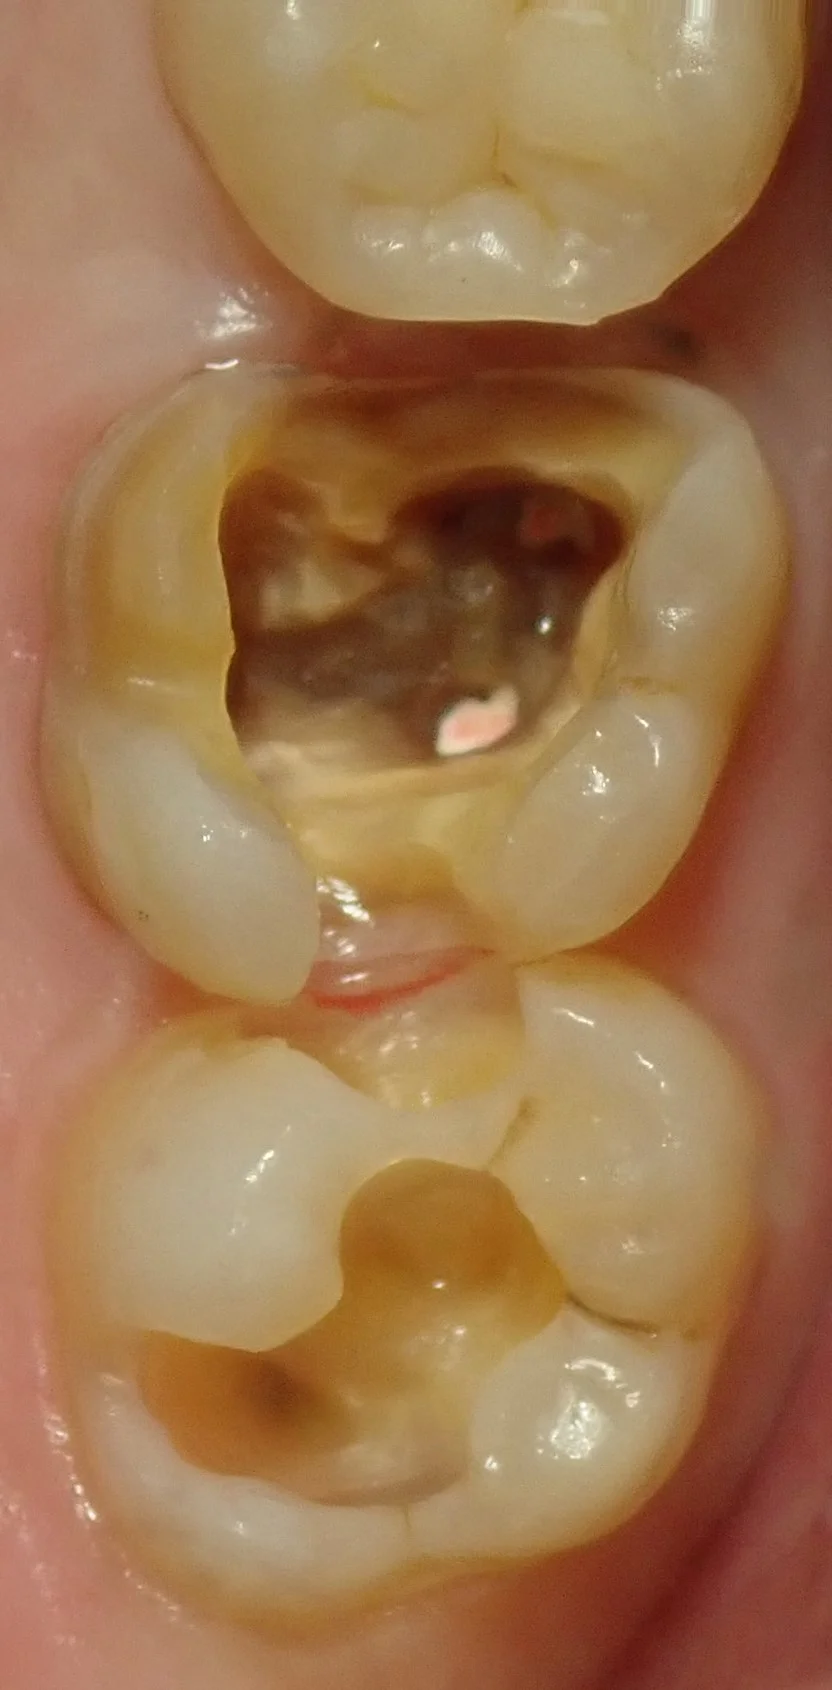

処置前の写真がこちらです。

大きな金属の詰め物が入っており、また後ろの歯にも大きく虫歯が出来ています。

どこかは少し分かりづらいかもしれませんが、金属を除去して・・・

虫歯を見えやすくすると・・・

こうなりました。

奥の方も非常に大きいのが分かるかと思います。

で、虫歯を取りきったのがこちらです。

左側の歯に見えているピンクのは神経の治療後に詰められるゴムです。

ある程度除去しておかないと、神経の治療の再治療リスクが上がるので、いつも、ある程度除去してから上物に移るようにしています。

深すぎてピントがあっていないですね・・・。

それだけでどれだけ深い虫歯だったのか分かるかと思います。